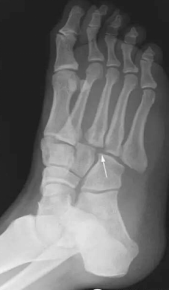

足舟骨骨折;跖骨骨折;楔骨骨折;跟骨骨折

粉碎性骨折;撕脱性骨折;疲劳性骨折

月骨脱位(1);跗跖关节脱位(2.3)